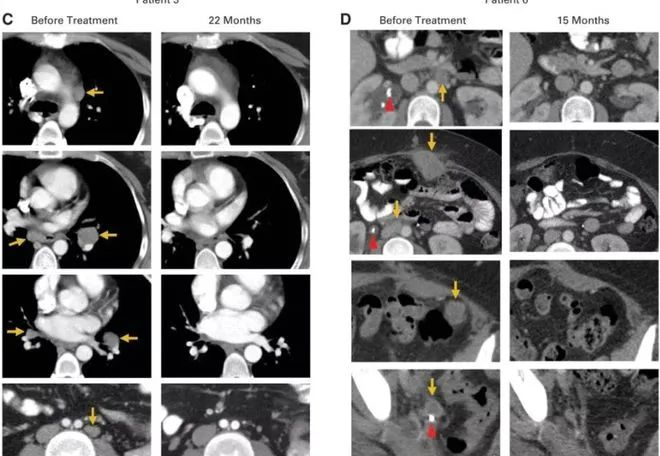

2018年,美國研究人員宣布,成功利用免疫療法徹底治愈一名宮頸癌患者,且已5年未復發,這也是世界范圍內首例使用免疫療法治愈宮頸癌的案例。

該被治愈的宮頸癌患者Sue Scott,當時36歲,經過多輪化療、放療和手術治療,依然沒有阻止癌細胞擴散,迅速侵入她的肝臟和結腸,并擠壓她的輸尿管。

隨后,Scott參加了一項由美國國家衛生研究院臨床中心(世界上從事生命科學研究最重要的研究機構之一)組織的免疫治療治療試驗,在該實驗中,醫生通過手術切除她的部分腫瘤,并且分離出免疫T細胞,然后研究人員將這些腫瘤浸潤淋巴細胞(TIL)進行改造和擴增并重新注入體內,形成一支免疫大軍,靶向攻擊癌細胞,最終成功將癌細胞“干掉”。

試驗的結果出人意料,幾個月后,Scott的腫瘤完全消失了。

2018年3月,她慶祝了癌癥康復5周年,醫生告訴她,她的癌癥已經完全治愈。